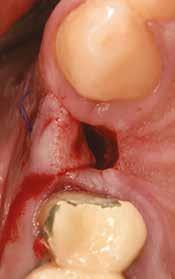

Az 50 éves nőpáciens az alsó és felső állcsont területén egyaránt panaszt (fájdalom, ráharapási érzékenység) okozó, harmadfokban mozgatható fogak miatt jelentkezett rendelőnkben. Az általános anamnézisben említést érdemlő betegség, műtét nem szerepelt. Az elvégzett klinikai és radiológiai vizsgálatok (1–2. ábra) alapján fogai reménytelen parodontális státusúnak bizonyultak, hosszú távon sem megtartásuk, sem protetikai célú felhasználásuk nem volt lehetséges. A parodontális prognózis a fogak eltávolításának abszolút indikációját jelentette. Ezáltal mindkét állcsontban teljes foghiány kialakulásával kellett számolnunk. A protetikai szemléletű, „visszafelé” tervezés elveit követtük a hosszú távú funkcionális, esztétikai siker és szöveti stabilitás elérése érdekében: mindkét állcsontban overdenture típusú fogpótlás készítése mellett döntöttünk. A megfelelő implant-protetikai rehabilitáció alapja az implantátumok megfelelő pozicionálása. A korábbi parodontális kórfolyamat következtében a processus alveolarisokat érintő eredendő csontdeficittel kellett számolnunk, amelyet tovább súlyosbíthatott volna a hagyományos extrakciós technikát követő involúciós atrófia. Ezért a páciens kivizsgálása és megfelelő előkészítése után a fog eltávolításával egy időben PRF

27 VI. ÉVFOLYAM – 2023. 4. SZÁM

Sticky Tooth segítségével kivitelezett alveolus prezerváció mellett döntöttünk, a megfelelő csontos és mukogingivális gyógyulás minőségi és mennyiségi elősegítése érdekében. A PRF készítmény mennyiségét, minőségét, kezelhetőségét és hatékonyságát jelentősen befolyásolják a páciens laborértékei, ezért kezelési protokollunk szerint a műtétet megelőzően minden esetben laborvizsgálatot végzünk (hemoglobin: 134 g/liter, hematokrit: 0,43, fehérvérsejt: 6,6 G/liter, CRP: 13,60 mg/liter, vércukor: 6,2 mmol/liter, összkoleszterin: 7,00 mmol/liter, triglicerid: 1,08 mmol/liter, HDL koleszterin 2,57 mmol/liter, LDL koleszterin 1,12 mmol/liter), D3 vitamin: 117,5 nmol/liter).

A fogak eltávolítása és az alveoláris csont megőrzésének és regenerációjának segítése céljából elvégzett augmentáció altatásban történt. Óvatos, atraumatikus extrakciót követően eltávolítottuk a parodontális és periapikális gyulladásos folyamatok eredményeként jelen lévő sarjszövetet. A bukkális csontfal hiánya és a tervezett vertikális augmentáció miatt indokolt membrántechnika megfelelő kivitelezése céljából a felső állcsonton mukoperioszteális lebenyt képeztünk (3–4. ábra). Az alveolus prezervációt Sticky Tooth, PRF és titánerősítésű teflon (PTFE-Ti) membránok segítségével végeztük el, a J. Choukroun által megadott vérvételi és centrifugálási protokoll (28) elveinek betartásával: kizárólag Process for PRF Duo Quattro System eszközöket, centrifugát, vérvételi egységet és csöveket, a membránok előállításához PRF Boxot használtunk. Az A-PRF és S-PRF csöveket a PomPac eljárásnak megfelelően 4 Celsius-fokra előhűtöttük. Az eltávolított fogak makroszkópos tisztítását és darabolását nagy fordulattal (300 000 RPM) fogászati turbinába helyezett gyémántfúróval végeztük, majd Tooth Transformer™ berendezéssel, annak gyári reagens rendszerével kezelt őrleményt nyertünk. A Sticky Tooth készítmény előállítása a PRF készítmény és az őrlemény

60/40 arányú keverésével történt (5–7. ábra), A-PRF és A-PRF/S-PRF membránokat készítettünk (8. ábra). Az alveólusokat a grafttal feltöltöttük, a felső front régióban vertikális augmentációt végeztünk a tervezett alveoláris csontmagasság elérésének céljából (9–10. ábra). A vertikális augmentáció támogatására titán mikrocsavarokkal rögzített, titánerősítésű teflonmembránokat alkalmaztunk, amelyekre egy rétegben A-PRF membránokat, és egy rétegben A-PRF/S-PRF membránokat helyeztünk. Az alsó állcsont esetében vertikális augmentáció nem volt szükséges, célunk az alveoláris kemény- és lágyszöveti struktúrák prezervációja volt, a graftot csak PRF memb-

ránokkal fedtük. A PRF membránok külön rögzítést egyik állcsont esetében sem kaptak (11–12. ábra). A mukogingivális lebenyt – annak megnyújtása nélkül – a helyére fektettük és varratokkal rögzítettük, per primam sebzárást nem végeztünk. A varratokat 2 hét után távolítottuk el, a varratszedésig a sebgyógyulás támogatására per os 1000 mg/nap C- és 12 000 NE/nap D-vitamint adtunk (28).